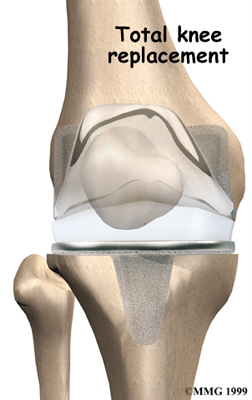

Artificial Knee Replacement

An artificial knee replacement is the ultimate solution for advanced knee OA.

Surgeons prefer not to put a new knee joint in patients younger than 60. This is because younger patients are generally more active and might put too much stress on the joint, causing it to loosen or even crack. A revision surgery to replace a damaged prosthesis is harder to do, has more possible complications, and is usually less successful than a first-time joint replacement surgery.

Related Document: FYZICAL-Galleria Therapy & Balance Centers Guide to Artificial Joint Replacement of the Knee